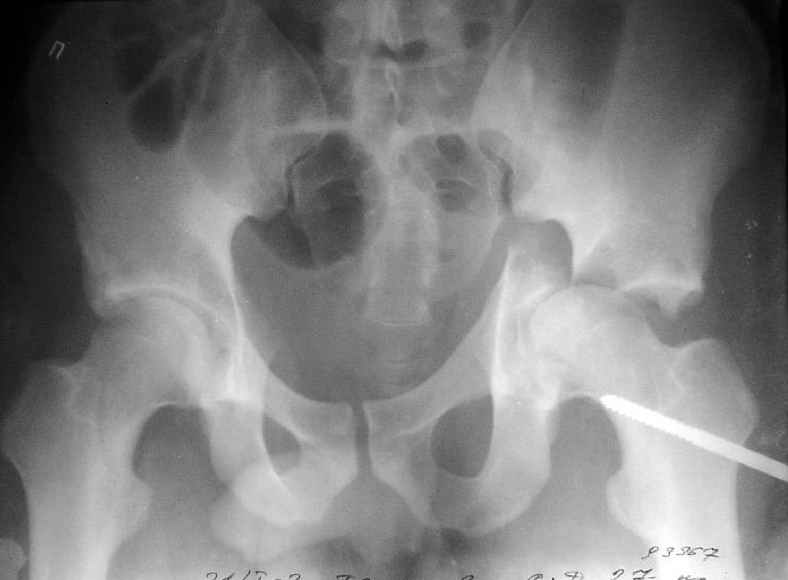

Пациент переведен в нашу клинику на 5 день после множественной травмы 25.01.2003 - двустороннее повреждение вертлужных впадин, разрыв левого

крестцово-подвздошного сочленения. Вывихи обоих бедер. В месте первичного поступления подвздошный вывих правого бедра вправлен

26.01.2003, наложено вытяжение за левую вертельную область.

Остеосинтез левой вертлужной впадины выполнен у нас 6.02.2003.

Вопрос: надо ли синтезировать задне-верхний край правой вертлужной впадины?